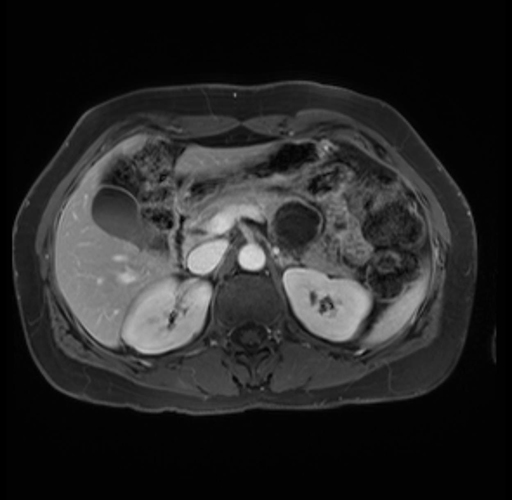

Imaging Analysis

Look through the patient's CT scan to identify any areas of concern for the necessary procedure.

Based on your CT findings, which issue(s) are present and would give reason for "planned slowing down moment(s)" in this case?

Considering a standard distal pancreatectomy procedure, what step(s) of the operation would you do differently in this case?